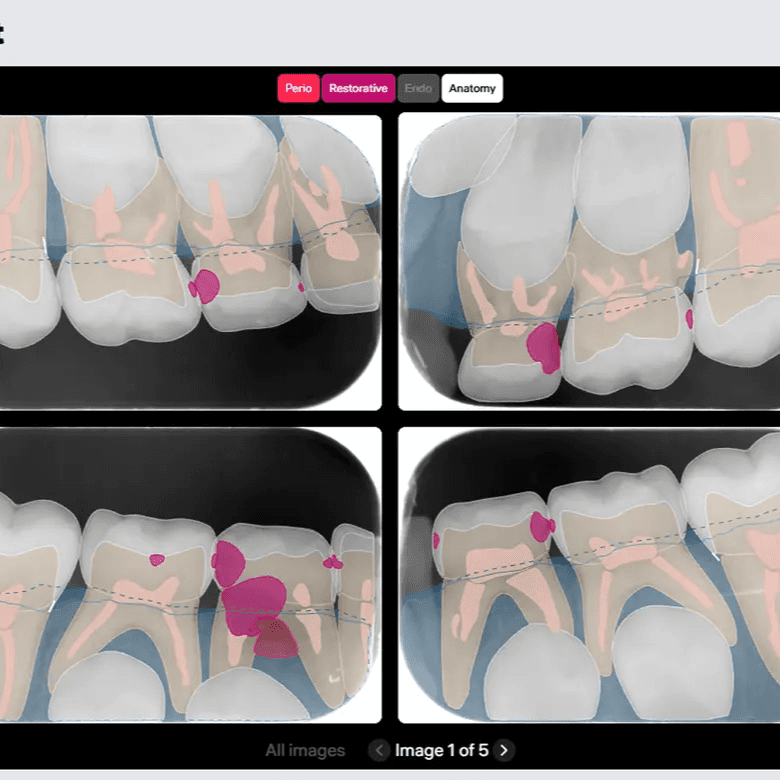

O DxPlan apoia diagnóstico e planeamento com análise por IA de imagiologia dentária 2D/3D, relatórios e visualização por dente — com decisão final sempre do profissional.

Capacidades Principais

Análise 2D/3D (CBCT) com deteção assistida por dente

Deteções assistidas de achados, organizadas por dente.

Relatórios 2D e 3D (CBCT) com medições, etiquetas por categoria e codificação visual

Exportação STL a partir de CBCT (quando aplicável).

Relatório final em PDF para partilha com o paciente